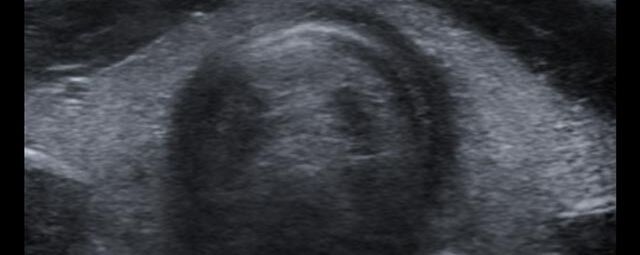

Die Sonographie ist ein bildgebendes Verfahren in der medizinischen Diagnostik, das mit Ultraschallwellen arbeitet. Ultraschall ist Schall mit einer Frequenz oberhalb der menschlichen Hörgrenze. Im medizinischen Bereich werden je nach Körperregion Ultraschallwellen in einem Frequenzbereich von ca. 3,5 – 18 Mhz verwendet. Die körpernahe Ultraschallsonde sendet durch einen piezoelektrischen Effekt kurze Schallwellenimpulse in den Körper. Ultraschall-Gel stellt den Kontakt zwischen Sonde und Körper her. Je nach Gewebeart werden diese Schallwellen im Körper unterschiedlich stark reflektiert. Anhand des zurückgesendeten Schallmusters kann das Ultraschallgerät Schnittbilder berechnen, auf denen die Organe des Körpers nach krankhaften Veränderungen untersucht werden können.